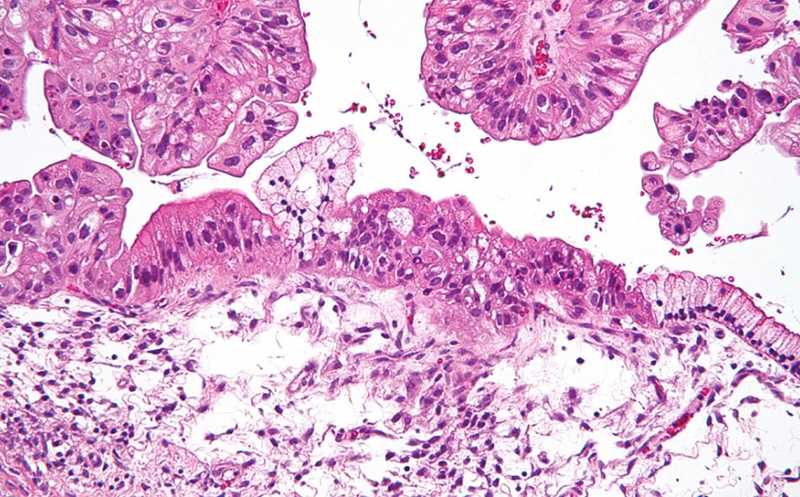

Ранняя диагностика — важнейший фактор для успешного лечения рака. Однако для некоторых видов онкологических заболеваний, в том числе рака яичников, она затруднена в связи с отсутствием клинических проявлений на ранних этапах и быстрым прогрессированием опухоли. Кроме того, рак очень разнообразен на молекулярном уровне, из-за чего бывает сложно подобрать диагностические биомаркеры. Ученые из США представили тест-систему для выявления вероятности рака яичников. Для анализа они использовали сыворотку крови, метаболом которой анализировался с помощью модели машинного обучения, а на выходе получали вероятность наличия рака яичников в баллах от -2 до 2.